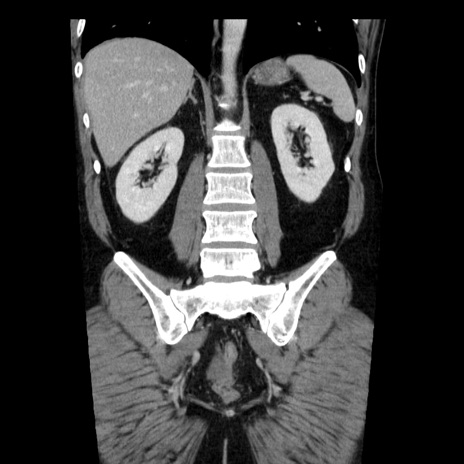

症例29(冠状断像)

【症例】40歳代男性

【現病歴】2日前から胃痛あり。徐々に周期的な激痛に変化した。本日になっても激痛があるため受診。

【身体所見】意識清明、BT 38-39℃台あり、腹部:膨満、やや硬、右下腹部に圧痛あり。

【データ】WBC 8500、CRP 23.26